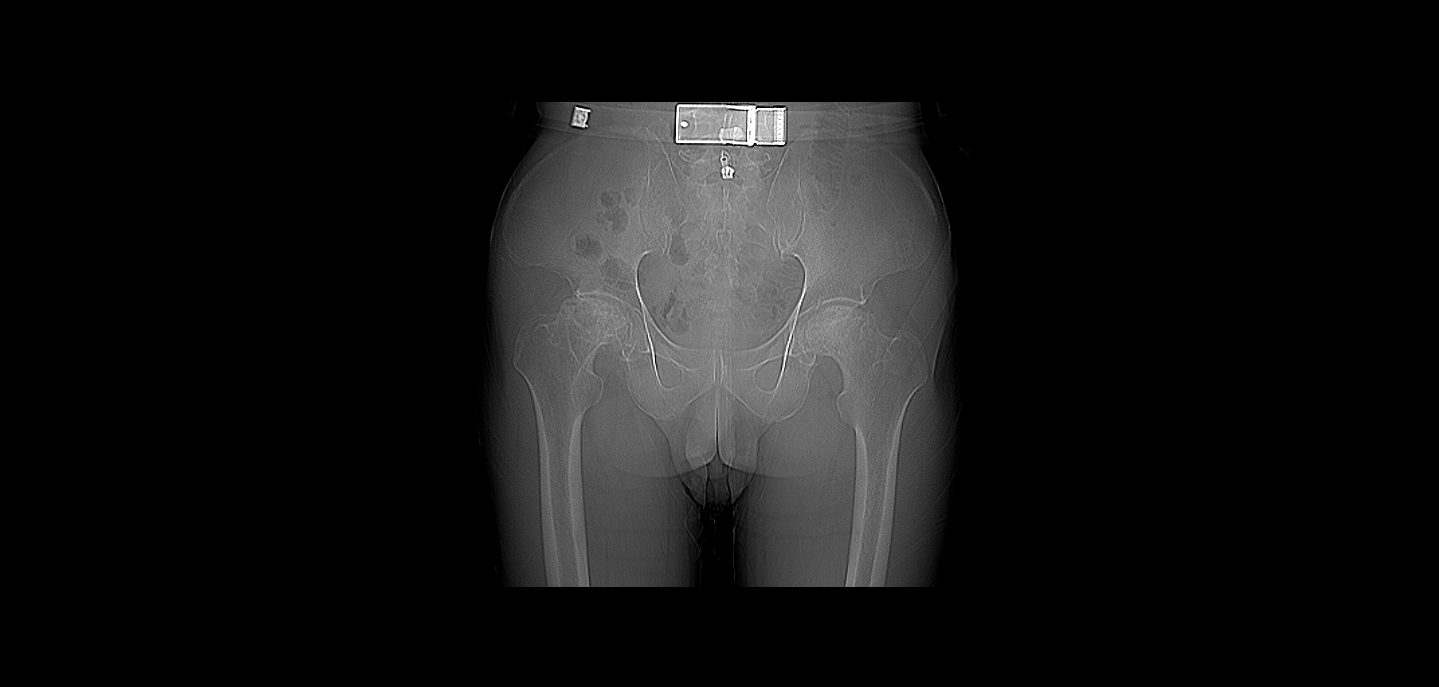

患者文伯,男,65岁,因双侧髋关节疼痛3年余于2017-04-11步行入病房。患者于3年前无明显诱因出现双髋关节疼痛,无其他部位放射痛,当时未重视,未行任何处理。2017年3月到宜恩县民族医院就诊,行双髋关节MR平扫提示:双侧股骨头坏死(未见报告),予活血化瘀及外用药物治疗后症状未见明显缓解,病情逐渐加剧,现已无法下地行走。查体:双侧髋关节周围压痛(+)、叩击痛(+),双髋活动受限,四肢肌力肌张力正常,肢体血运、感觉正常。入院后行双髋关节CT平扫提示:双侧股骨头无菌性坏死。于2017-4-14送手术室在全麻下行“双侧髋关节置换术”,术程顺利,术后患者恢复可,可自行下地行走,双髋关节疼痛已缓解。

术前1